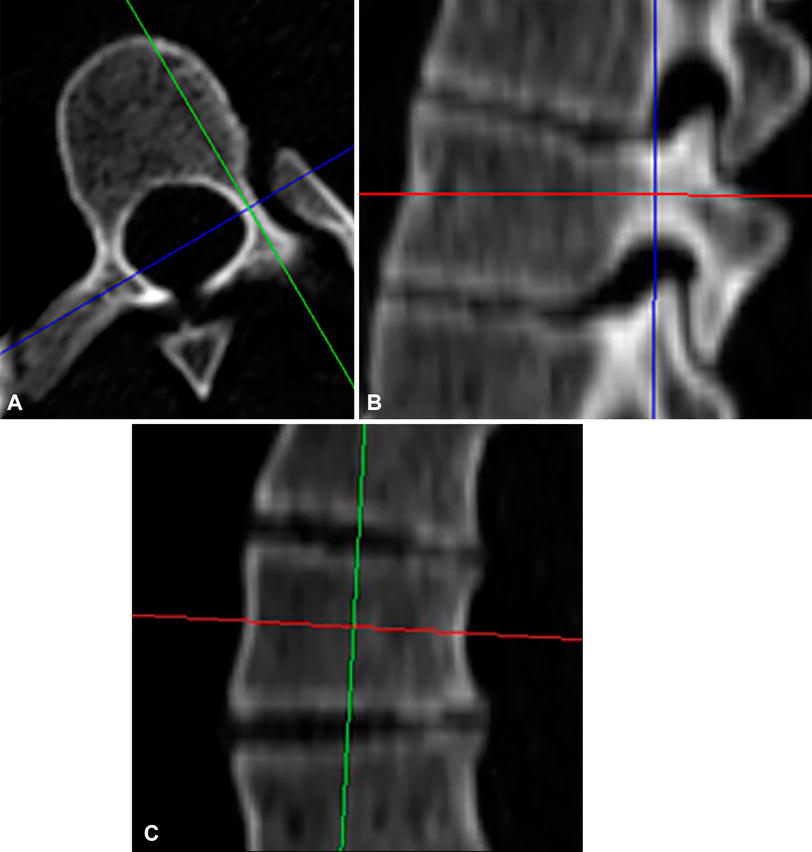

The local (A) axial viewing plane with a sagittal slice (green line) in line with the pedicle axis, (B) sagittal viewing plane with an axial slice (red line) in line with the pedicle axis, and (C) coronal viewing plane with an axial slice (red line) approximately parallel to the superior and inferior endplates are shown.